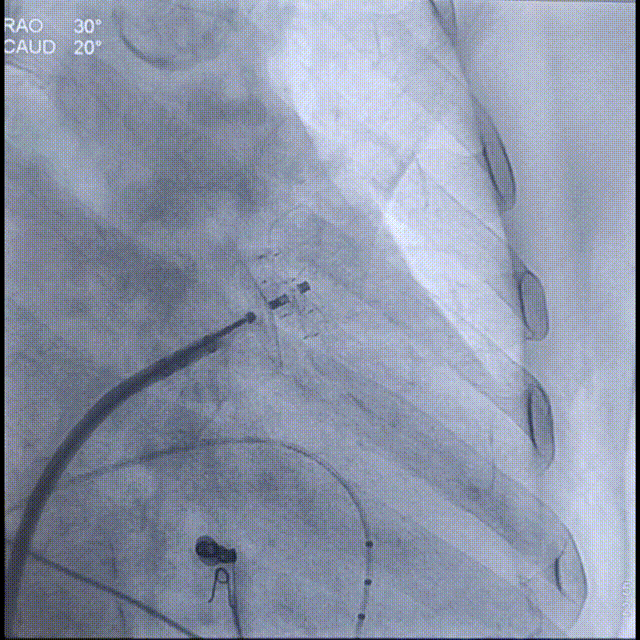

Laager®封堵器2631型号封堵盘展开过程

Laager®封堵器2631型号固定盘展开后造影

换用Laager®封堵器2631型号后造影提示位置良好,多体位下造影见封堵良好,封堵盘上缘在心耳口内,无残余分流;